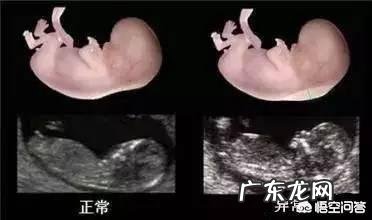

除了唐氏筛查,怀孕早期的nt检查也是筛查唐氏儿的一种方法 。nt检查也称为颈后透明带扫描,在胎宝宝后颈皮肤下积聚的液体可以通过超声波进行测量,医生会通过仪器详细的测量介于皮肤和组织之间的空隙厚度,如果颈后透明带厚度为3mm,胎宝宝可能会患有某种染色体疾病或者是发育不良 。